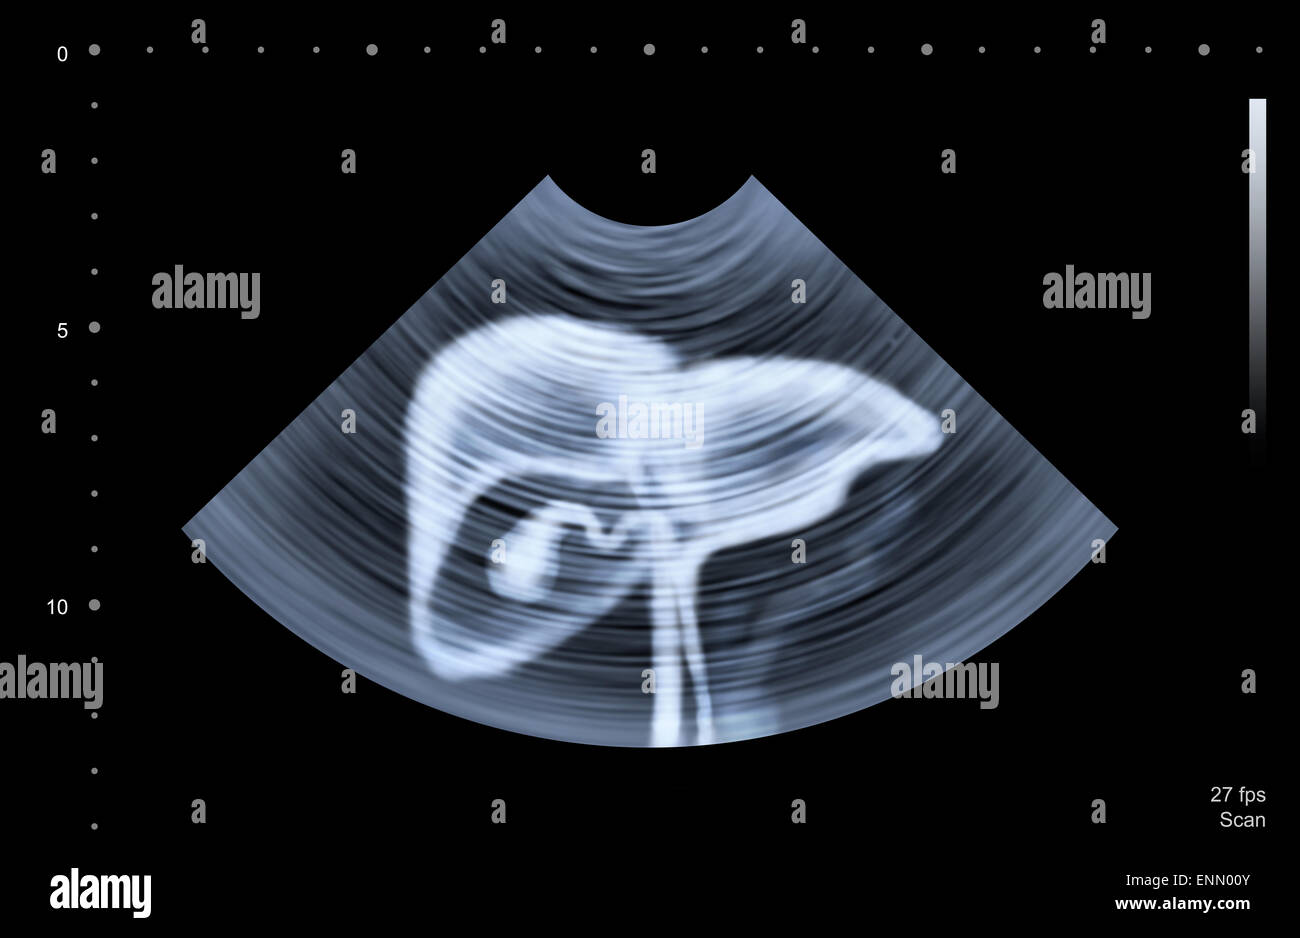

Ultrasound scan of human liver Stock Photo Alamy Liver In X Ray Cirrhoses) is the common endpoint of a wide variety of chronic liver disease processes which cause hepatocellular necrosis. Mri is used to image blood vessels (without using contrast), ducts, and hepatic tissues. Assessment of liver size is commonly made on ultrasound or ct, although gross hepatomegaly may be. A liver scan is a specialized radiology procedure used to examine the. Liver In X Ray.

Healthy liver, ultrasound scan Stock Photo Alamy Liver In X Ray Mri is used to image blood vessels (without using contrast), ducts, and hepatic tissues. It is used to see if liver cancer has spread to the lungs. Cirrhoses) is the common endpoint of a wide variety of chronic liver disease processes which cause hepatocellular necrosis. Mri is superior to ct and ultrasonography for. A liver scan is a specialized radiology. Liver In X Ray.